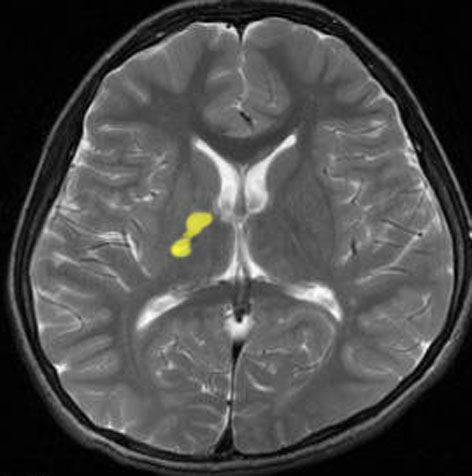

もう一つは,高次脳機能障害や緩徐進行性の片麻痺で発症する小児の大脳基底核ジャーミノーマ basal ganglia germinomaです。この腫瘍も腫瘤陰影が全く見えず,大脳半球の委縮像のみが画像上の所見であることがありますが,この大脳基底核germinomaの画像所見は特有なものです。CT/MRIガイド定位的生検術によりgerminomaの確定病理診断をつけることはできますが,大脳基底核germinomaは出血しやすくて脳内血腫という合併症を生じることが稀ならずあるので,T2/FLAIR画像で内包に限局するような小さな病変のみの場合は生検術は避けた方がよいです。メチオニンPETで高集積が認められ,この検査は診断的価値が高いといえます。血清髄液のHCG値がごく微量に陽性値となります。

- レンズ核,内包あたりに,T2/FLAIRでボッとした影がみえます

- ガドリニウム増強されません

10代の男児で,非常にゆっくり1年くらいかけて左片麻痺が進行しました,痙性片麻痺です。落ち着きのない性格でもありました。血清HCG-beta 0.1で陽性でした。この病変は内包後脚の小さなものですから,定位生検術でさえもリスクが高いので行いません。出血のリスクというわけではなく,組織採取で内包高脚のcompactな白質を損傷して症状を悪くするからです。ご両親とよく話し合って病理診断なしで治療を開始します。ICE化学療法4コースと全脳照射25.2Gy/14fr で治療しました。ICE化学療法開始後からは片麻痺の悪化傾向が停止して,症状が改善傾向に向かいました。やがて,走れるようにもなりました。